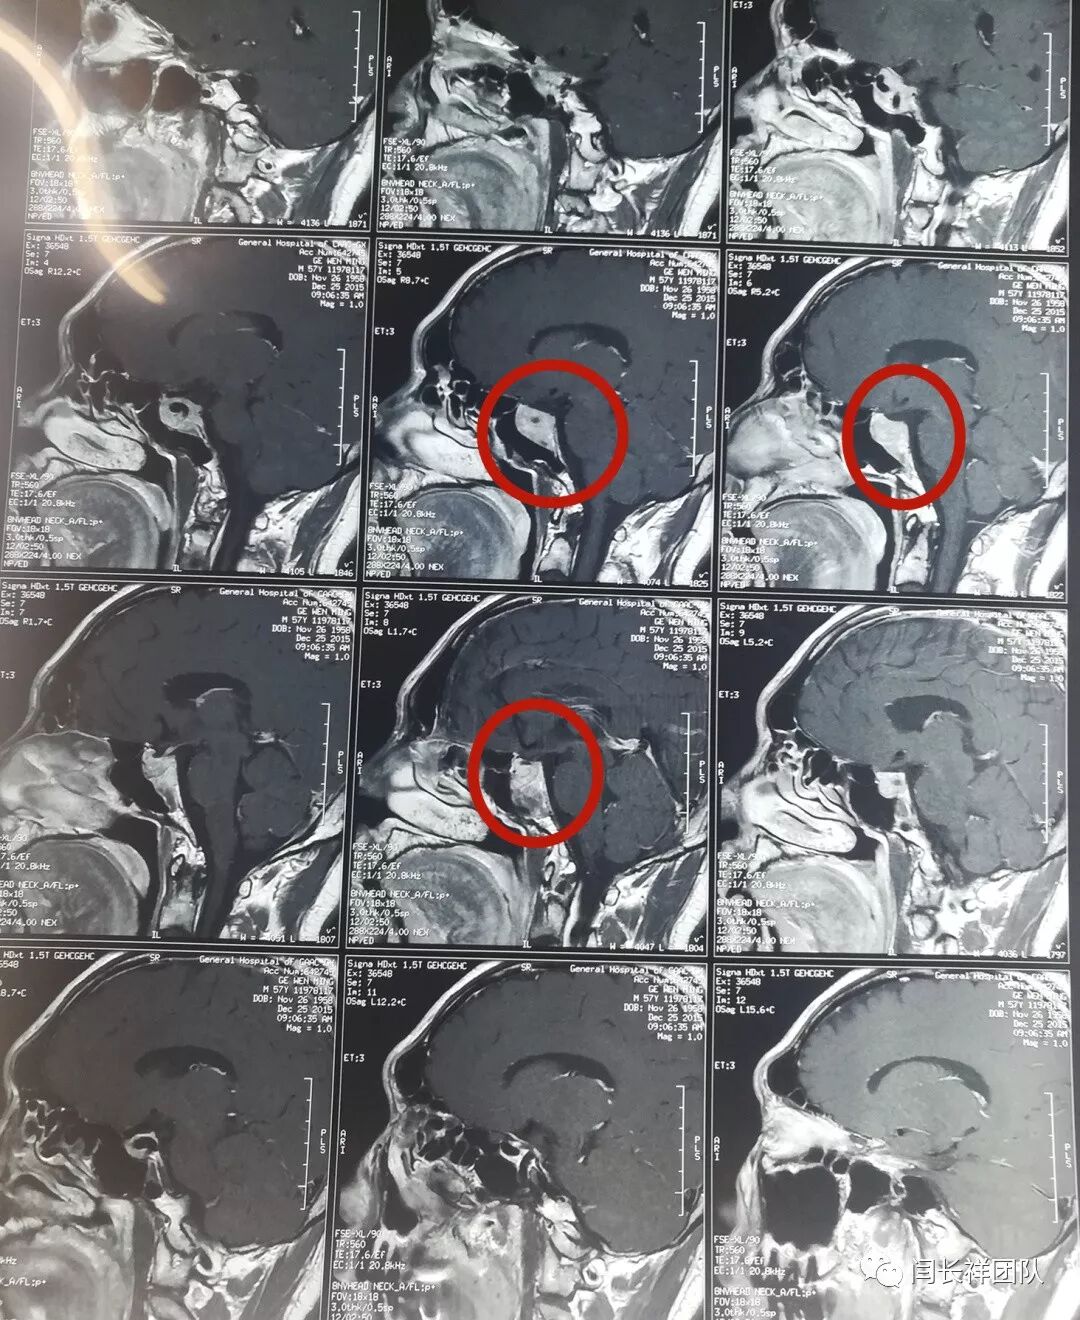

老葛在朋友的介绍下来到三博脑科找到闫长祥。做了头颅核磁后,闫长祥告诉他——你这是垂体瘤。

再做个垂体激素检查。结果出来后不得了——血清泌乳素水平达到2740ng/ml。而正常人的血清中泌乳素水平最高值一般不会超过20ng/ml。现在可以明确诊断了——泌乳素型垂体瘤。

从以上视频看来,老葛恢复得不错,不但气色好了,身体状态、精神状态都好了。最关键的是,垂体瘤比以前缩小了很多,质地也不像之前那么实心了。没开刀,垂体瘤也治愈了一大半。

再来看看今天的泌乳素水平化验单,结果怎么样了呢?服用溴隐亭两年,泌乳素水平从2000多下降到12.7ng/ml!